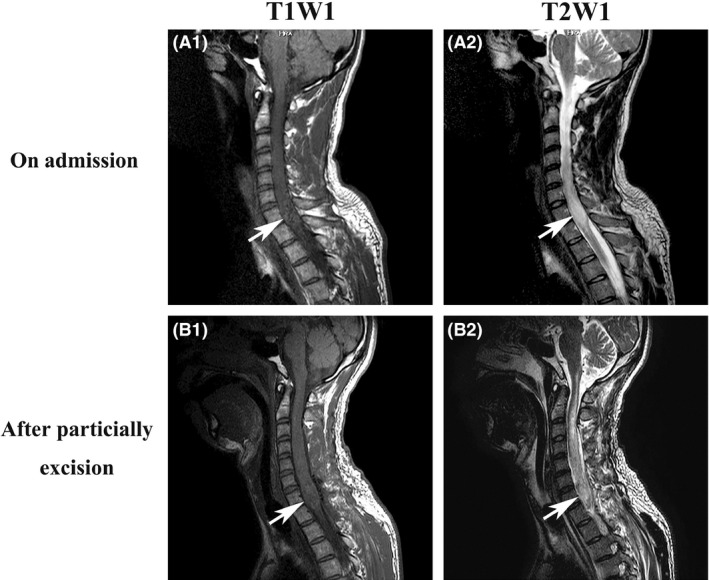

A 32‐year‐old Asian man presented with a 2‐week history of numbness and muscle weakness in his legs, with no preceding infectious symptoms. At initial hospital admission, he complained of inability to walk independently and cervical pain. Guillain–Barré syndrome was initially suspected based on his cerebrospinal fluid examination, which revealed protein cell dissociation (polynuclear, 0/mm3; mononuclear, 4/mm3; normal range of total cells [<5.0/mm3]; protein 62 mg/dL, normal range [≤45 mg/dL]; glucose 59 mg/dL, normal range [45–80 mg/dL]). Several days later, he developed quadriplegia and gradual onset sensory disturbance. His respiratory condition worsened, with respiratory muscle paralysis causing respiratory failure. He was intubated and transferred to our hospital, where an enlarged spinal lesion (C7–T1) was identified on cervical magnetic resonance imaging (MRI) (high signal on T2WI and low signal on T1WI; Fig. 1A). The patient had an unremarkable medical history and no familial history of spinal tumors.

Figure 1.

Intraspinal tumor on cervical magnetic resonance imaging (MRI) of a 32‐year‐old man. A, MRI images on admission. (A1) T1W1, (A2) T2W1. B, MRI images after tumor incision biopsy, partial excision, and tracheostomy. (B1) T1W1, (B2) T2W1. Arrows indicate an intraspinal tumor.

The patient was diagnosed with ARF caused by the spinal tumor. We undertook emergent decompression of C3–T2 and extended duraplasty of C6–T1 on day 3 of admission and also started steroid pulse therapy (prednisolone 1000 mg/day for 3 days), which did not resolve his symptoms. A tumor incision biopsy with partial excision and a tracheostomy was carried out on day 10, as contrast cervical MRI showed an intraspinal tumor (Fig. 1B).